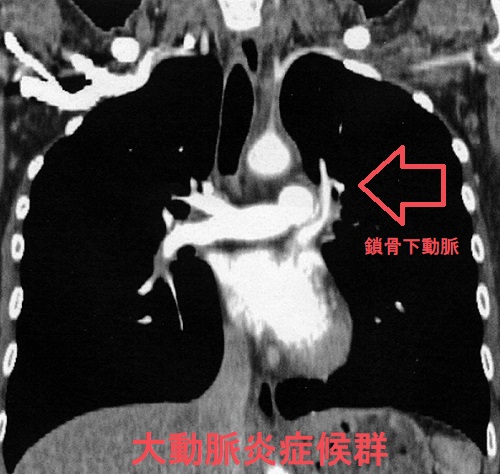

大動脈炎症候群(高安動脈炎、脈なし病)の画像所見は、

- 造影CT;

肥厚した血管壁では、中心に比べて辺縁部(内膜、外側)が強く造影される(double ring enhancement)

罹病期間が長いと動脈壁の石灰化、内腔の狭窄・拡張、動脈瘤を認める

大動脈炎症候群 単純CT (東京レントゲンカンファレンス)